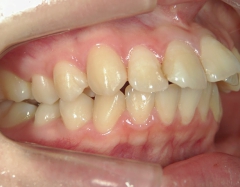

矯正歯科 治療前

no.6_8296_治療前_右.jpgno.6_8296_治療前_正面.jpgno.6_8296_治療前_左.jpg